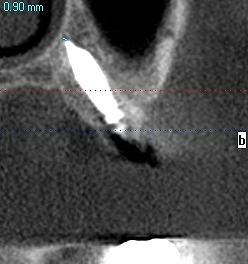

4番のインプラントになります

5番の傾斜埋入にインプラントになります